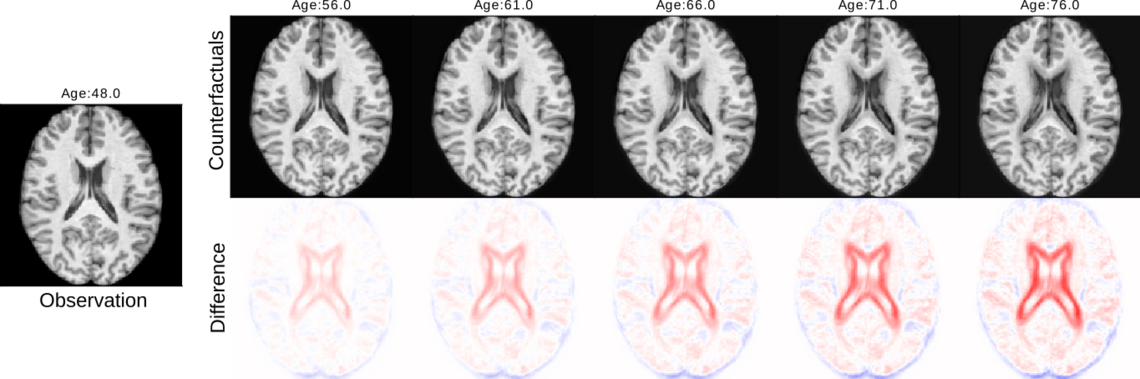

Previous studies have reported that risk factors for cardiometabolic diseases are associated with accelerated brain aging. However, these studies were primarily based on standard correlation analyses, which do not unveil a causal relationship. While randomized controlled trials are typically required to investigate true causality, we investigate an alternative method by exploring data-driven causal discovery and inference techniques on observational data.